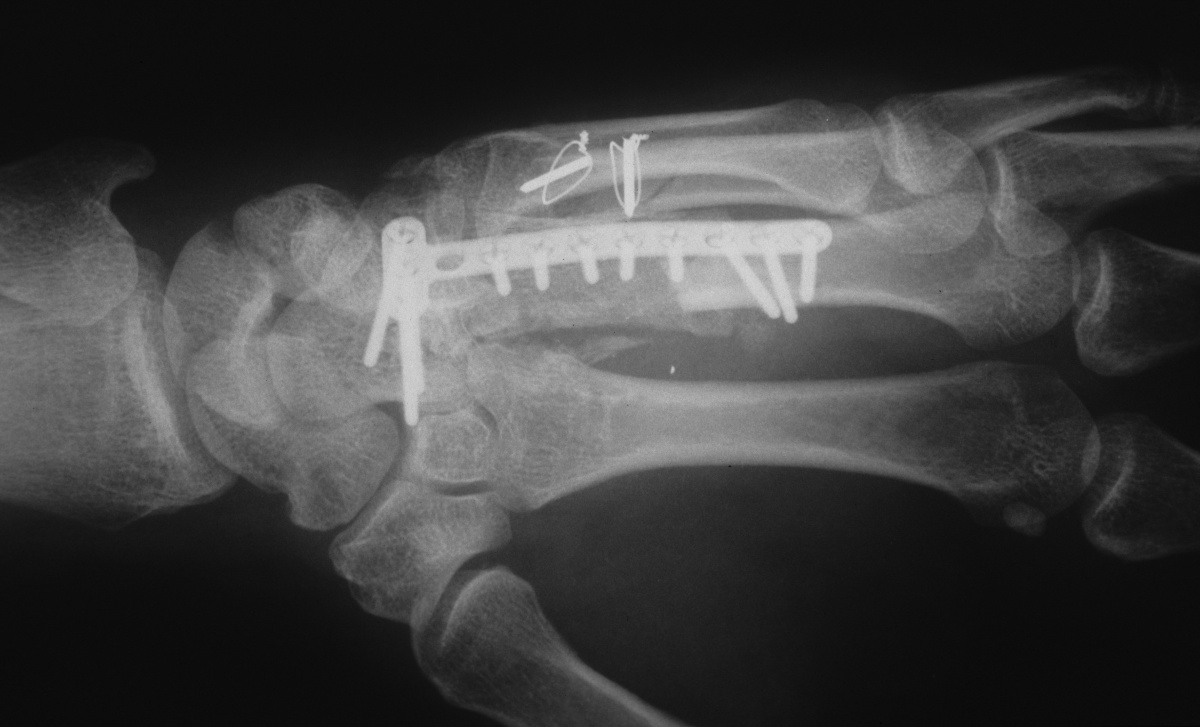

| Fixation of

bicortical iliac crest graft incorporating

carpometacarpal arthrodesis. |